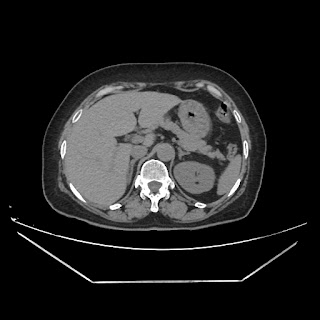

A CT abdomen revealed a left adrenal cortical tumor.

CT images: